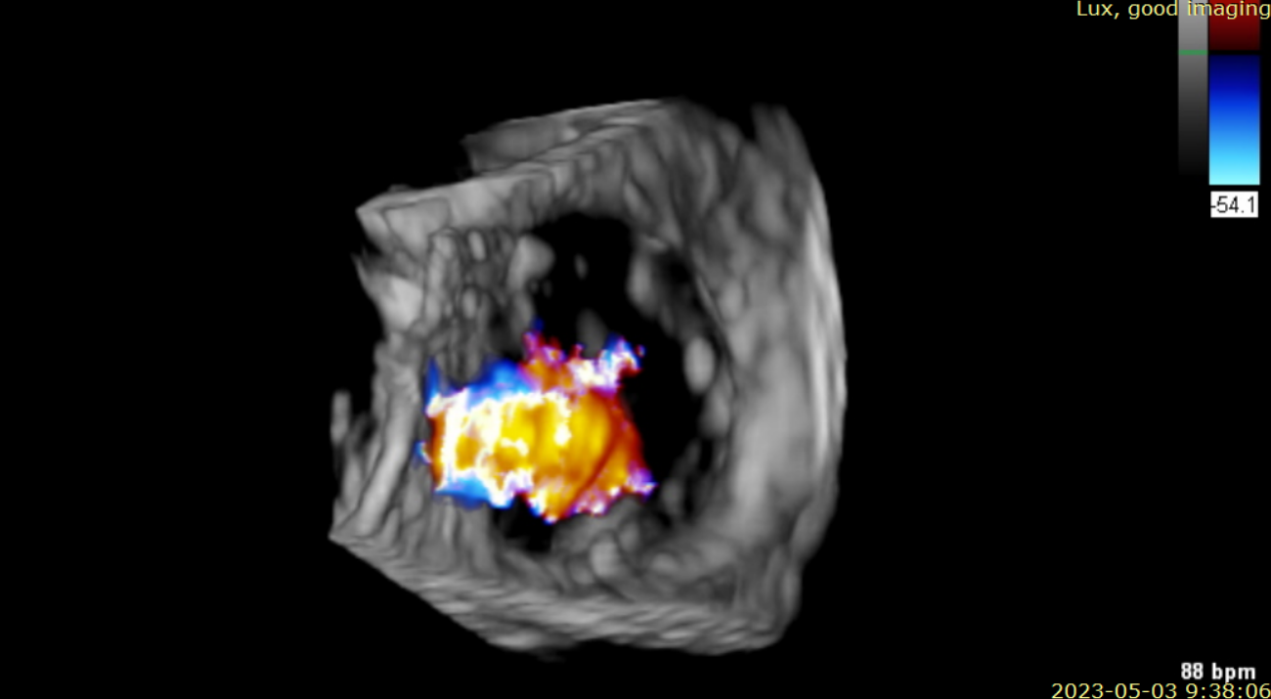

術(shù)后超聲提示僅殘余輕微瓣周漏

術(shù)后Azeem Latib教授對(duì)LuX-Valve Plus經(jīng)血管三尖瓣置換系統(tǒng)的器械性能和治療效果大為稱贊,并且認(rèn)為L(zhǎng)uX-Valve Plus的手術(shù)體驗(yàn)非常好。從治療效果來(lái)看,術(shù)后即刻超聲顯示三尖瓣反流幾乎完全消失,血流動(dòng)力學(xué)改善顯著,患者恢復(fù)快。在面對(duì)復(fù)雜解剖結(jié)構(gòu)、超聲影像質(zhì)量不佳、有起搏導(dǎo)線干擾時(shí),Lux-Valve Plus也體現(xiàn)了極強(qiáng)的適應(yīng)性。Thomas Modine教授參與了術(shù)中指導(dǎo),他同樣再次肯定了LuX-Valve Plus術(shù)中操作的便捷性,認(rèn)為L(zhǎng)uX-Valve Plus容錯(cuò)率高,對(duì)術(shù)中影像的依賴小,并表達(dá)了后期希望可以更多地應(yīng)用LuX-Valve Plus三尖瓣置換系統(tǒng)于臨床實(shí)踐,讓更多的三尖瓣重度反流患者盡早獲益,改善預(yù)后。